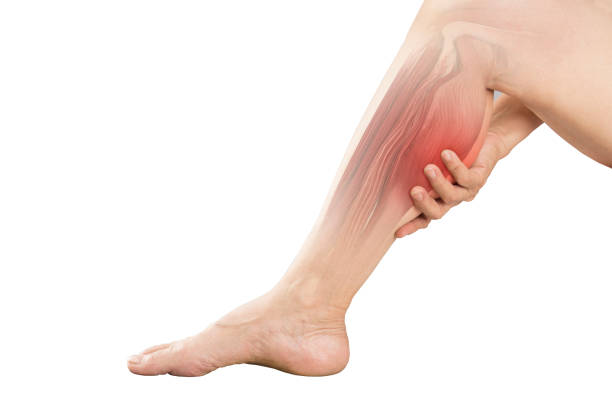

다리 전기 오는 느낌의 원인과 다양한 질환들

다리 전기오는 느낌의 발병 원인이 워낙 다양해서 본인이 어떠한 이유로 이런 느낌이 오는 것인지 정확한 질환을 잘 파악하신 후에 적절한 치료 방법을 찾는 것이 중요합니다.

꼭 전문가에게 정확한 진단을 받으셔서 엉뚱한 치료 하지마시고 증상을 방치하지 않도록 유의하시기 바랍니다.